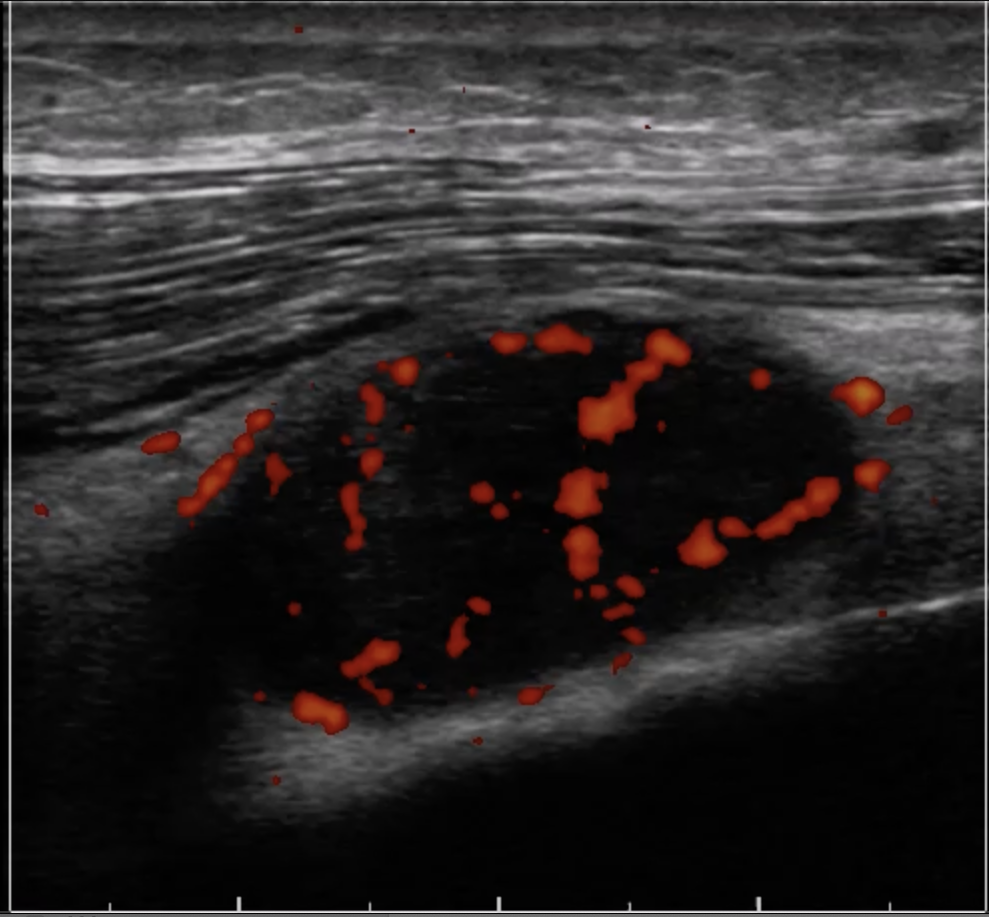

アキレス腱の炎症反応

(整形外科でアキレス腱炎と診断された例)

見たい場所をリアルタイムで画像化できるため、筋肉や関節を動かしながら観察できます。

筋肉や腱の滑走性などを確認することでリハビリするべき部位がより明確になったりもします。

怪我の回復の経過も確認でき、スポーツ復帰をするときの指標にしたりもします。